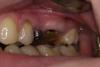

fmn Опубликовано 8 октября, 2013 Поделиться Опубликовано 8 октября, 2013 Здравствуйте, уважаемые коллеги. Перебирая архив, наткнулся на небольшой кейс 2009 года. Надеюсь, он покажется интересным и, возможно, для кого-то полезным.Исходная ситуация Пластика - туннель с ССТ 3 месяца 2 Ссылка на комментарий

doca Опубликовано 8 октября, 2013 Поделиться Опубликовано 8 октября, 2013 вам тут удлинять уже надо,а не рецессии закрывать,ну а тому,кто под ноль зуб спилил-по рукам 1 Ссылка на комментарий

fmn Опубликовано 8 октября, 2013 Автор Поделиться Опубликовано 8 октября, 2013 вам тут удлинять уже надо,а не рецессии закрывать,ну а тому,кто под ноль зуб спилил-по рукамСогласен, мезиально БШ маловато. Ссылка на комментарий